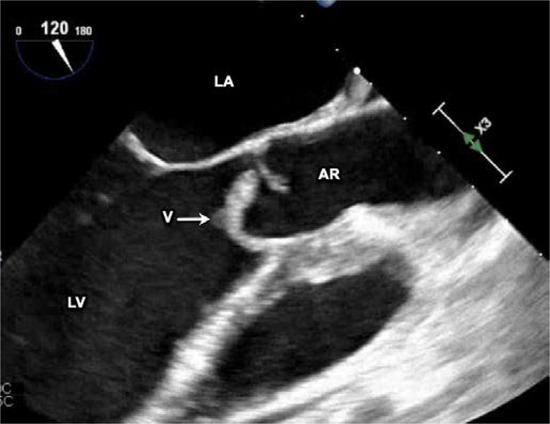

Introduction: Neisseria elongata, which is part of the normal oropharyngeal bacterial flora, can be an aggressive organism causing serious infections including infective endocarditis. N. elongata infective endocarditis is rare and no current guidelines exist to direct antibiotic selection and/or duration of treatment. Case report: We report a case of infective endocarditis due to N. elongata and a review of the literature. Our patient is a healthy young woman, who was found to have an aortic root abscess with valve perforation requiring valve replacement. Discussion: N. elongata infective endocarditis typically affects the left cardiac chambers and is associated with high risk of embolization. A transesophageal echocardiogram should be performed as part of the initial workup to assess the extent of infection, as a high percentage of patients develop perivalvular abscess formation and/or valve perforation. Most patients require prolonged antibiotic therapy and early surgical intervention. Conclusions: This case demonstrates the potential severity of N. elongata endocarditis. Further studies are needed to establish management guidance. Full article

Figure 1